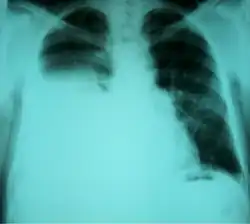

Chest X-ray showing a hepatic hydrothorax in a person with cirrhosis